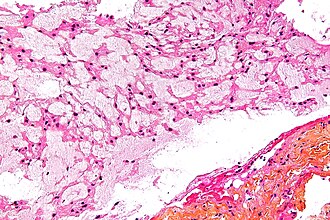

Chordoma. HPS stain. | |

| LM | physaliphorous cells (also bubble cells) - very large clear bubble with a sharp border, bubble does not compress nucleus; islands of cells surrounded by fibrous tissue; myxoid background |

- Architecture: islands of cells surrounded by fibrous tissue.

- Also described as "lobulated" architecture; may not be apparent.

- Myxoid background - grey extracellular material, variable amount present.

- Mixed cell population:

- Abundant eosinophilic cytoplasm.

- Physaliphorous cells or bubble cells - key feature.

- Have a very large clear bubble with a sharp border; bubble does not compress nucleus - nucleus may be in bubble.